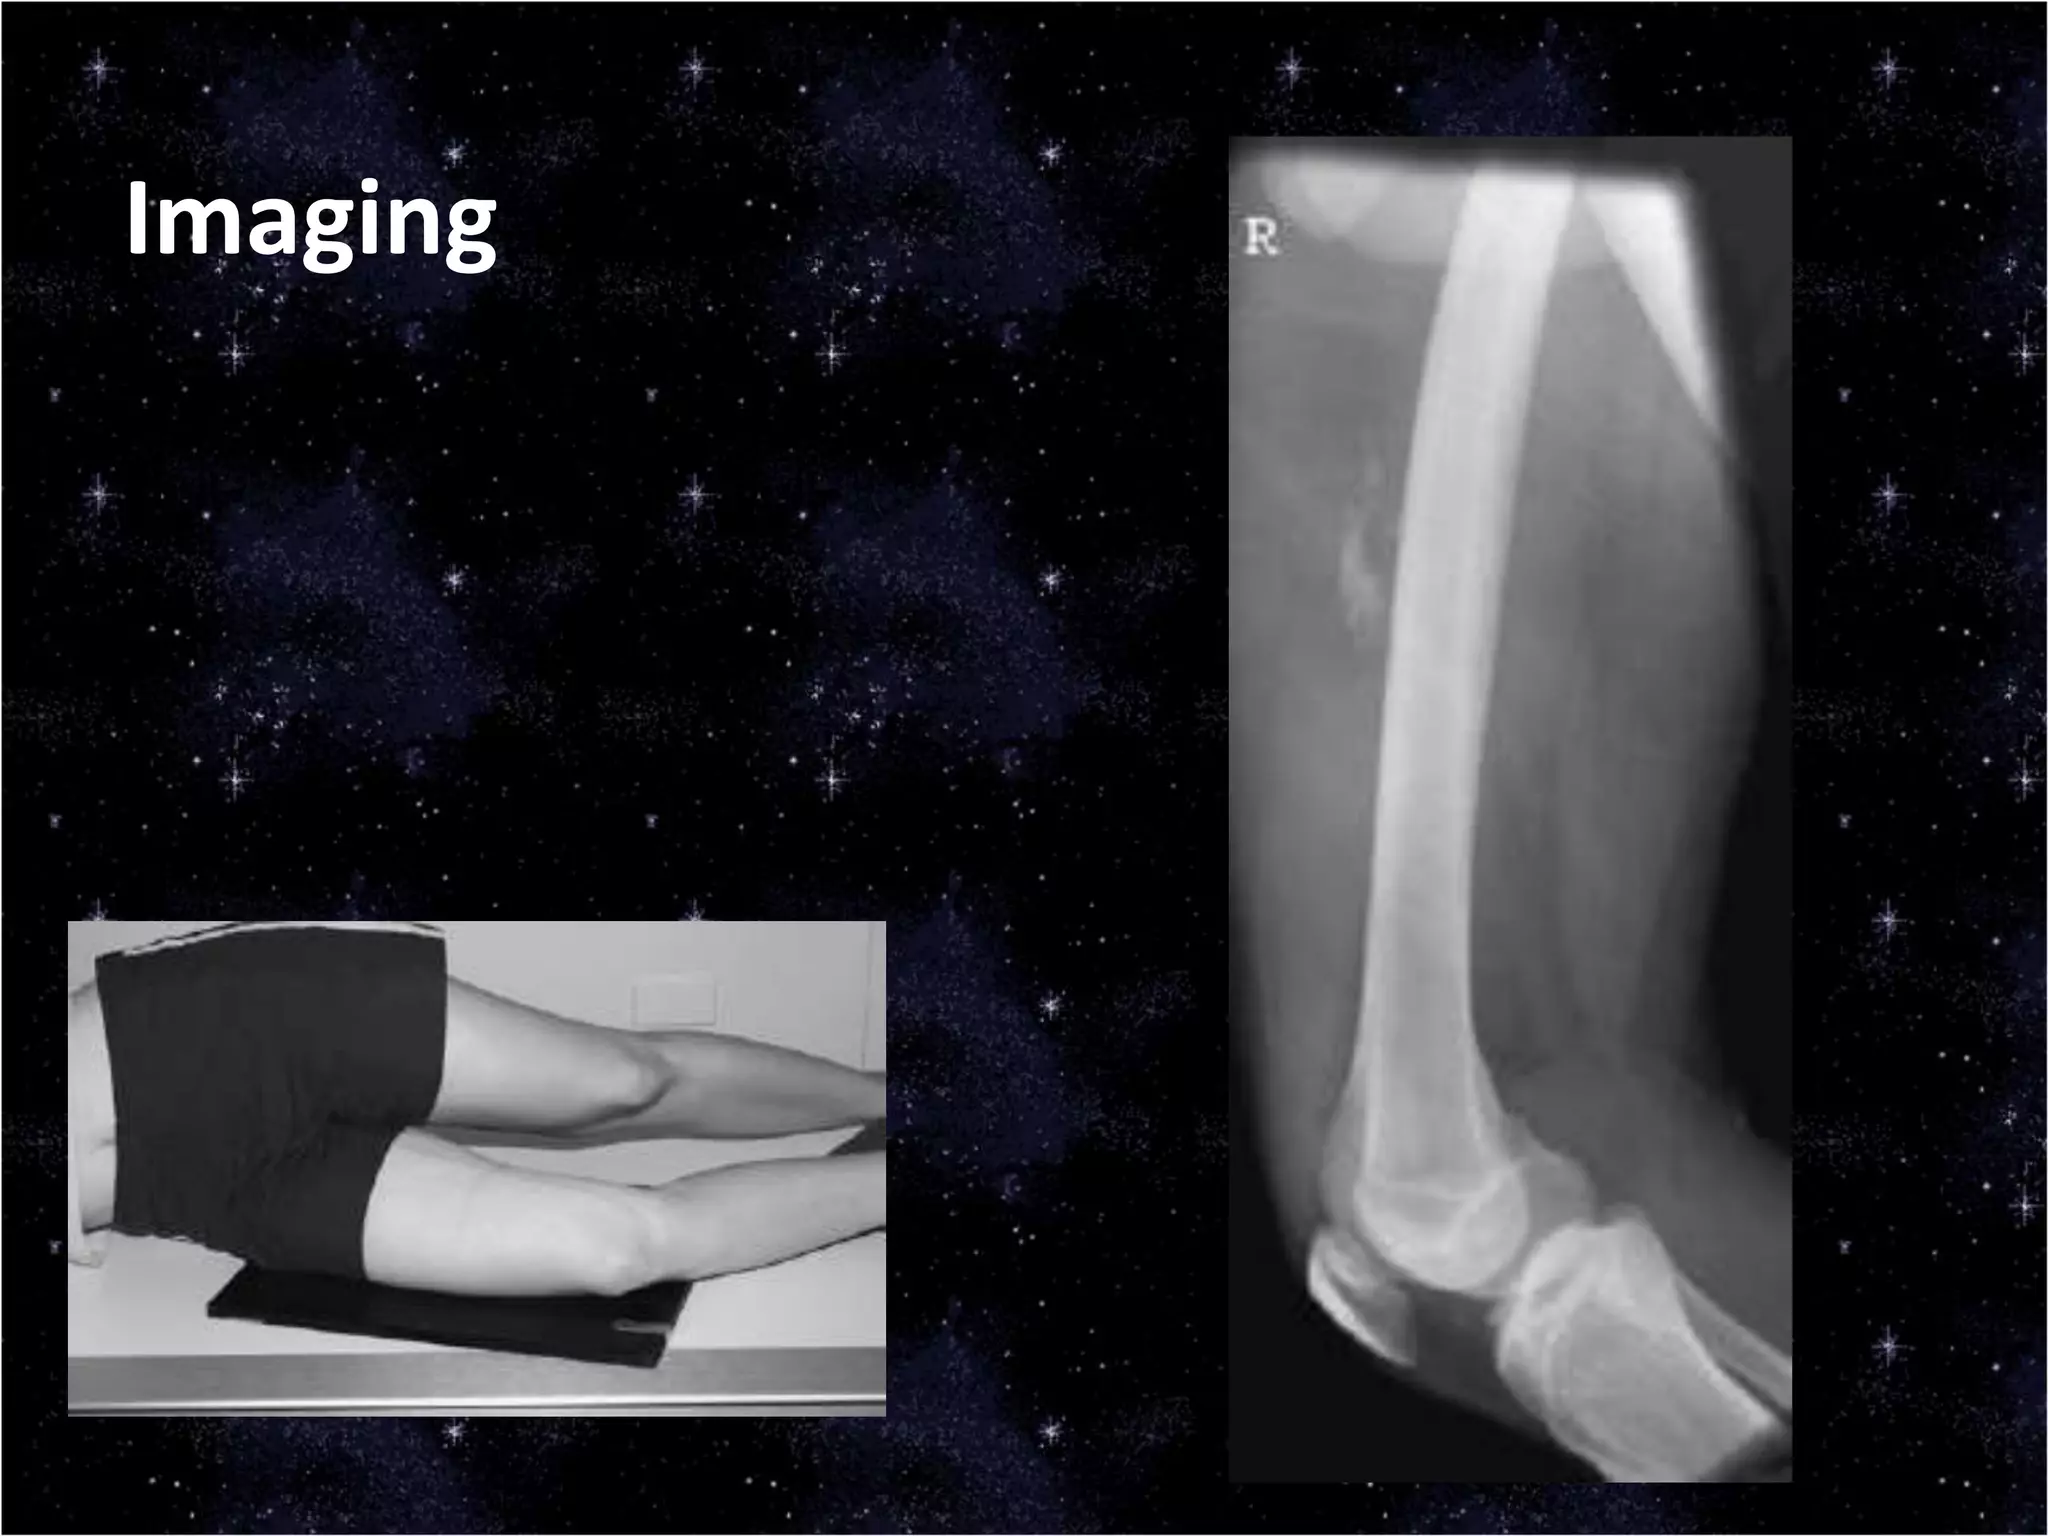

This document discusses trauma to the pelvis, hips, knees, ankles, and feet. It covers anatomy, imaging techniques, and types of fractures and dislocations that can occur in these areas. The types of fractures discussed include pelvic ring fractures, acetabular fractures, and fractures of the femur, tibia, fibula, and bones of the foot. Imaging views used include AP, inlet, and outlet views of the pelvis. Dislocations and fractures of the knee, ankle, and foot joints are also examined.